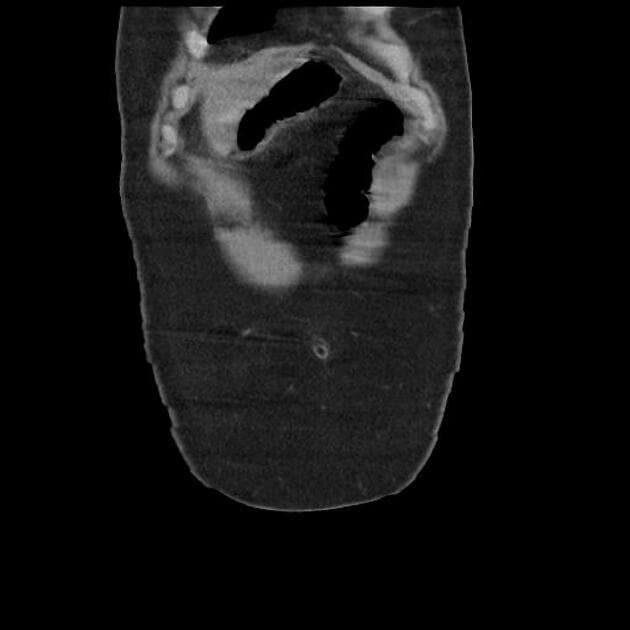

Axial C+ portal venous phase

- Chụp CT cho thấy tình trạng phù nề lan tỏa của tuyến tụy (pancreatic gland), liên quan đến hiện tượng tăng đậm độ mỡ viêm quanh tụy (peripancreatic inflammatory fat stranding) và dịch tiết viêm giảm tỷ trọng (low attenuation inflammatory exudate) bao quanh tụy, lan xuống các đoạn tá tràng, rãnh cạnh đại tràng (paracolic gutters) và khoang chậu (pelvic cavity).

- Ghi nhận tràn dịch màng phổi trái mức độ nhẹ (mild left-sided pleural effusion).

- Gan giảm tỷ trọng (decreased density) do xâm nhiễm mỡ (fatty infiltration).

- Hình ảnh học phù hợp với viêm tụy cấp (acute pancreatitis). Men amylase và lipase của bệnh nhân đã được xét nghiệm và cho thấy tăng đáng kể.

- Viêm tụy cấp (acute pancreatitis)

Viêm tụy cấp là một tình trạng viêm tụy thường do sỏi mật hoặc lạm dụng rượu. Các dấu hiệu trên CT bao gồm giãn to tụy lan tỏa, tăng đậm độ mỡ quanh tụy và dịch viêm lan ra các khoang lân cận như rãnh cạnh đại tràng và khoang chậu. Tràn dịch màng phổi, đặc biệt bên trái, có thể do viêm toàn thân hoặc kích thích cơ hoành. Xét nghiệm men amylase và lipase tăng cao giúp khẳng định chẩn đoán. Chẩn đoán hình ảnh đóng vai trò quan trọng trong đánh giá mức độ nặng, phát hiện biến chứng và loại trừ các chẩn đoán phân biệt như thủng tạng rỗng hoặc tắc mạch mạc treo.